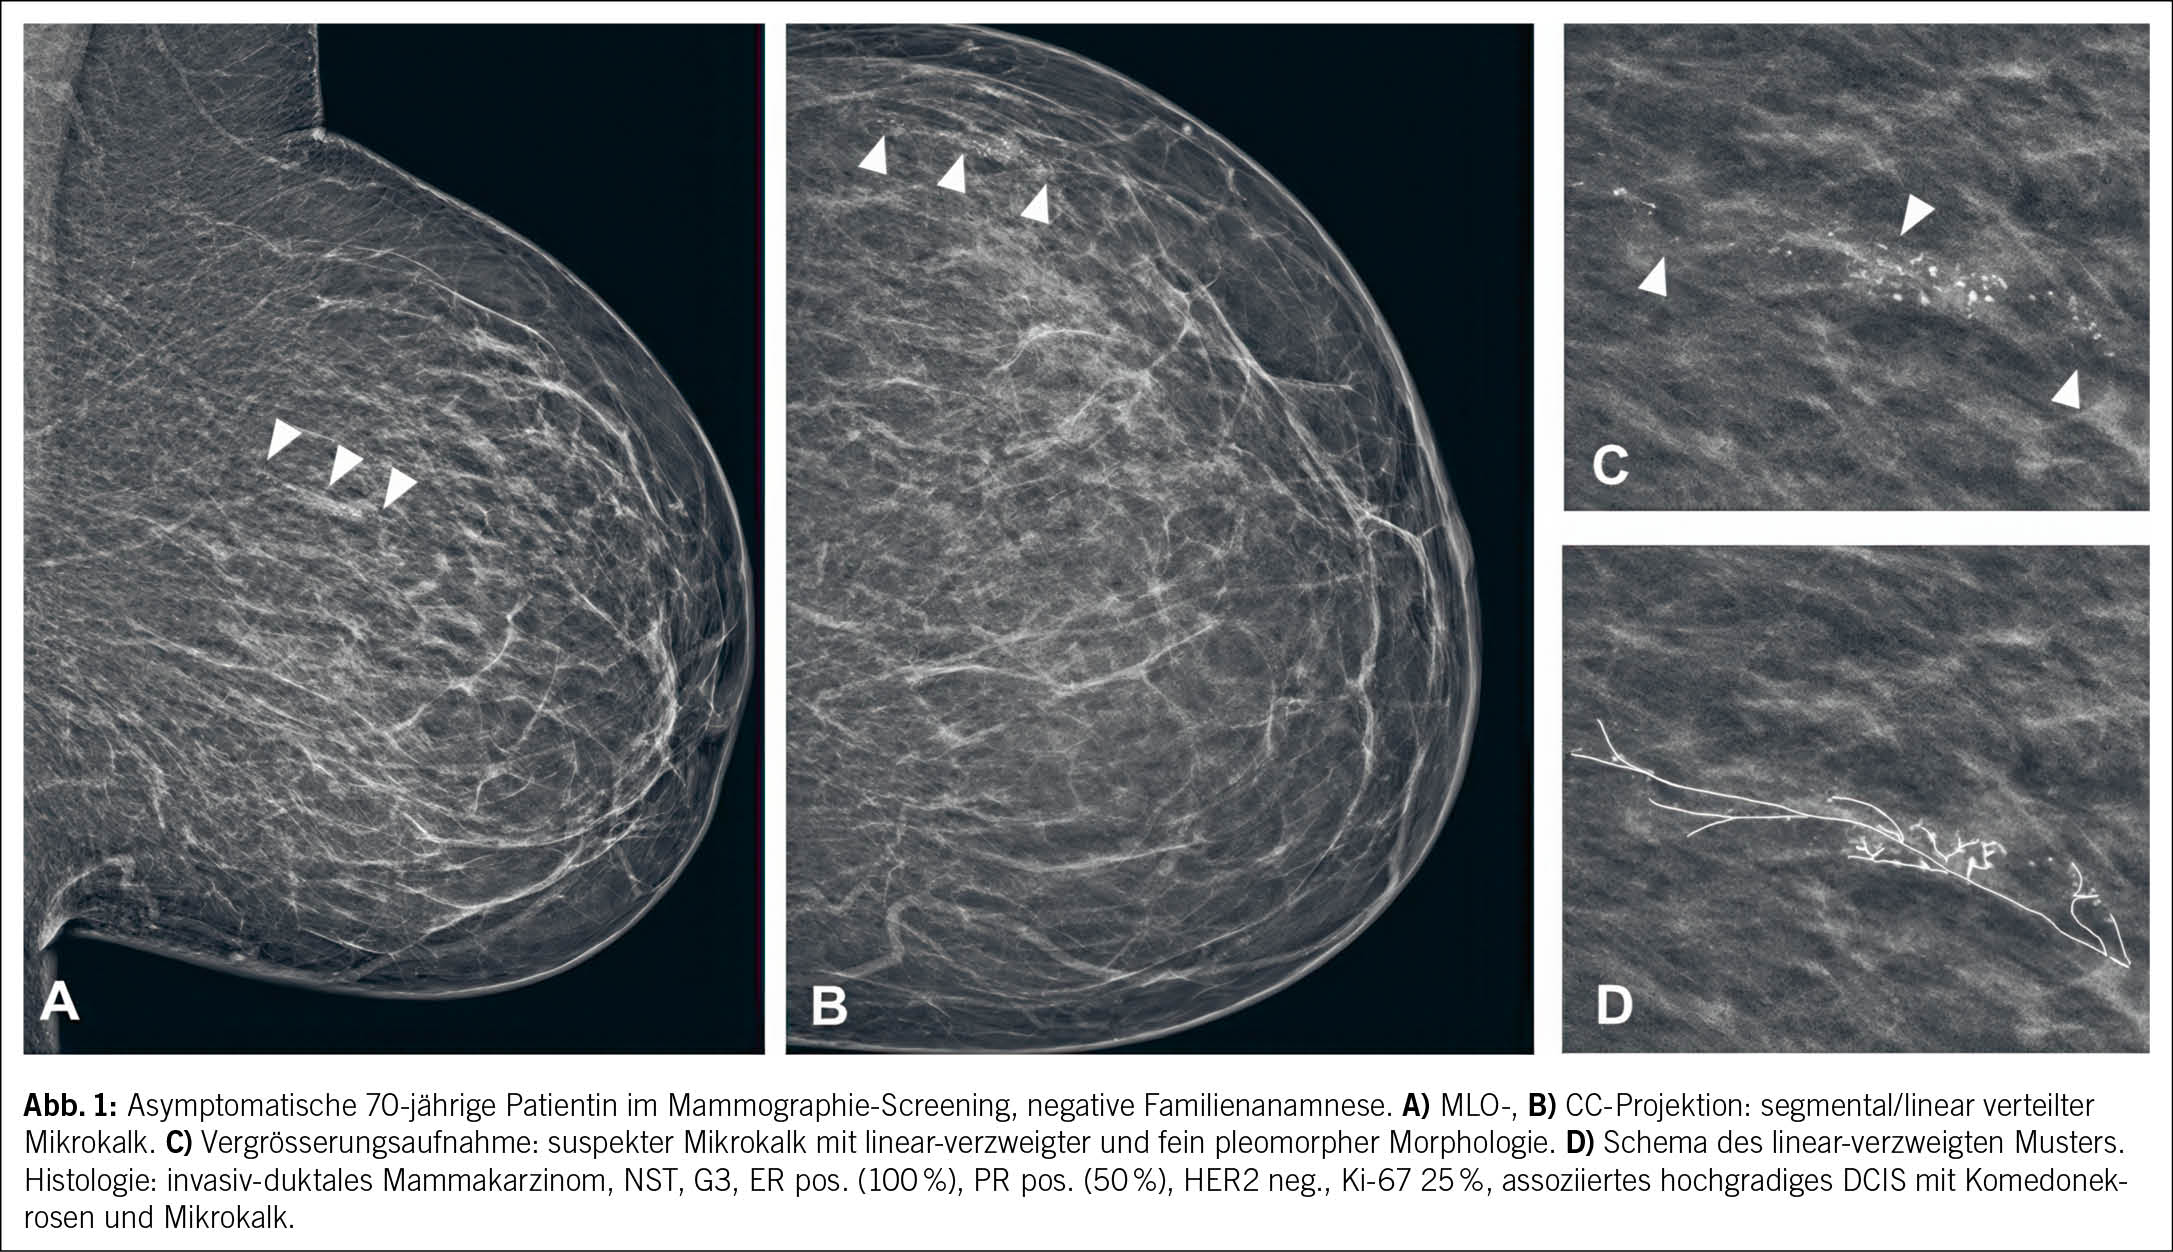

Menschen mit Adipositas leiden unter einer zentralnervösen Regulationsstörung der Energiehomöostase, insbesondere der Steuerung des Hunger- und Appetitempfindens. Dabei spielt eine unzureichende Wirkung neuroendokriner Feedbacksignale aus der Peripherie, wie beispielsweise Leptin und Insulin, im Sinne einer zentralnervösen Leptin-/Insulin-Resistenz eine bedeutende Rolle. Daraus resultierend ergibt sich bei Menschen mit Adipositas im Vergleich zu Nichtbetroffenen gemäss dem «Behavioral Balance Model» (1) ein physiologisch erhöhter «bottom-up»-Antrieb zur Gewichtzunahme (Abb. 1).